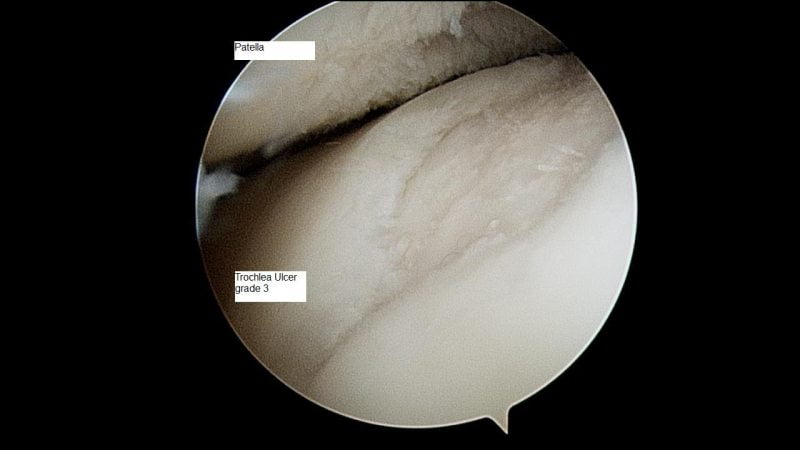

Это реальное изображения головки бедренной кости при 2-3 стадии артроза. Посмотрите внимательно и подумайте, поможет ли в этом случае гимнастика?

Чаще всего, именно на такой разрушения суставов пациенты начинают заниматься лечением. Но уже поздно не только гимнастикой заниматься, но и делать любые другие процедуры.